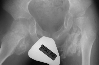

XRAYS:

Radiographic findings of HO on plain films is evident at 4-6 weeks, usually trabeculation is absent. Payne and DeLuca(10) define HO in soft tissues as radiodensity 5 mm from the femoral shaft and not initially adjacent to the femur which is periosteal callus and HO is usually a flocculent pattern.Technetium three-phase bone scan is positive in the initial phase of HO and is 90% sensitive in 2-4 weeks after injury. Return to baseline is 7-12 months after injury(14). Bone scans may be used to assess the level of maturity of the HO. Computed tomography can differentiate native vs. ectopic bone by revealing the osseous architecture(14).Computed tomography may also be useful in planning surgical approach. Magnetic resonance imaging can demonstrate soft tissue swelling but receives only limited signal from calcified tissue(14). Ultrasound has been shown to detect HO earlier than plain radiographs in eight consecutive patients by Thomas and Amstutz (17).